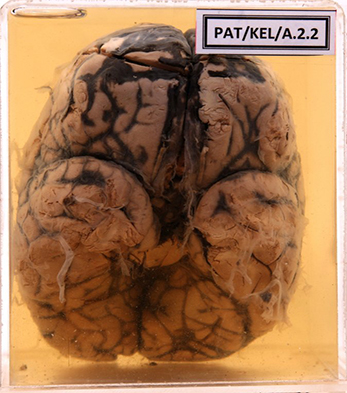

A.2.2 Subarachnoid haemorrhage

Massive subarachnoid haemorrhage covering both frontal poles and seeping down the sagital sinus extending over the posterior part of the vertex.